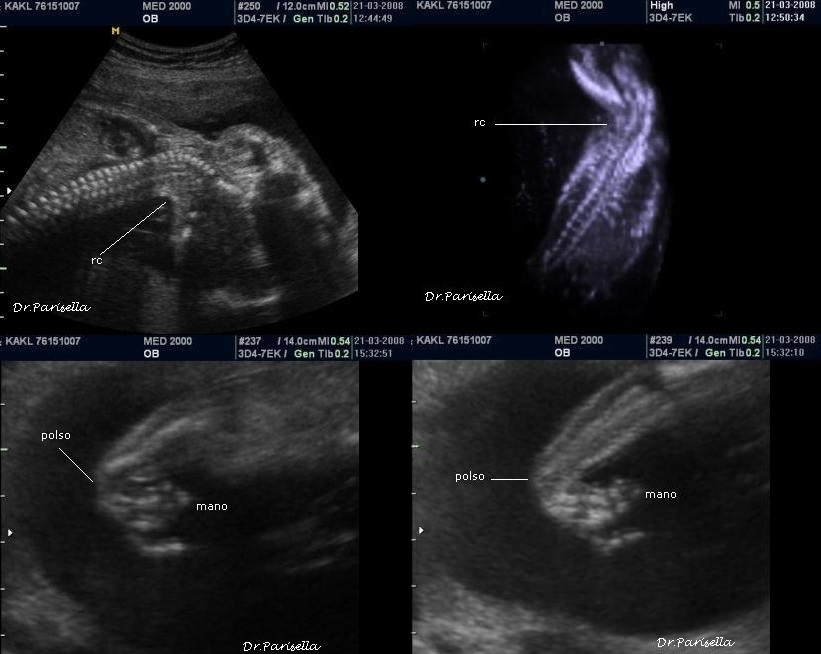

La Diagnosi Prenatale Ecografica si basa su:

2) contratture multiple.